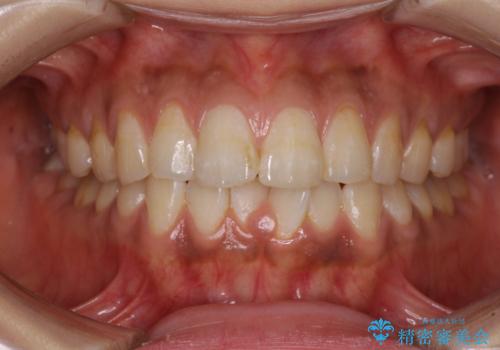

上下前歯の前歯と腫れやすい歯肉 インビザライン矯正で改善